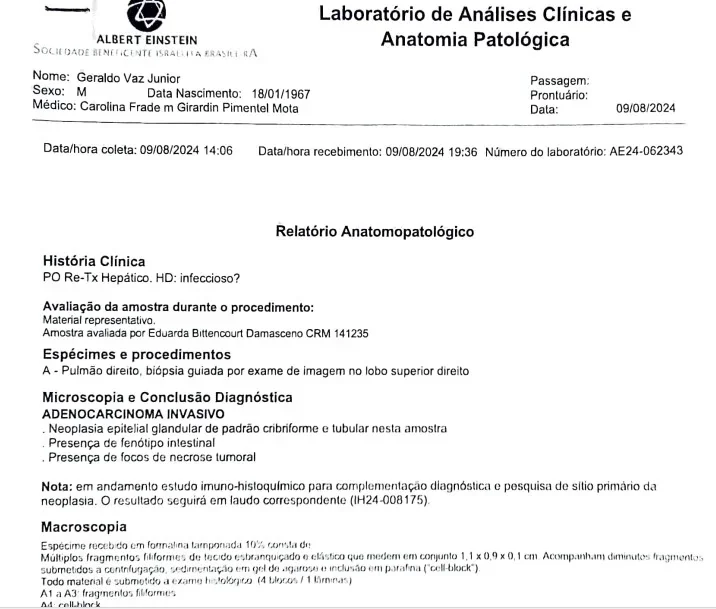

A análise foi realizada no Hospital Albert Einstein, mesmo local onde o transplante foi feito e onde o paciente atualmente realiza quimioterapia. Em agosto do ano passado, médicos identificaram metástases nos pulmões de Geraldo. O laudo apontou que o tumor foi transmitido com o órgão, possivelmente por células isoladas ou micrometástases que só se manifestaram posteriormente.

A médica Caroline Daitx, especialista em medicina legal, avaliou os documentos e afirmou que o resultado do DNA é conclusivo. Segundo ela, o tumor apresenta cromossomos XX, típicos de uma mulher, enquanto Geraldo possui XY, o que comprova que o câncer veio da doadora do fígado. O Ministério da Saúde, inicialmente, negou relação entre o transplante e o câncer, mas depois reconheceu que os exames do doador não mostraram sinais de doença e que os protocolos foram seguidos.